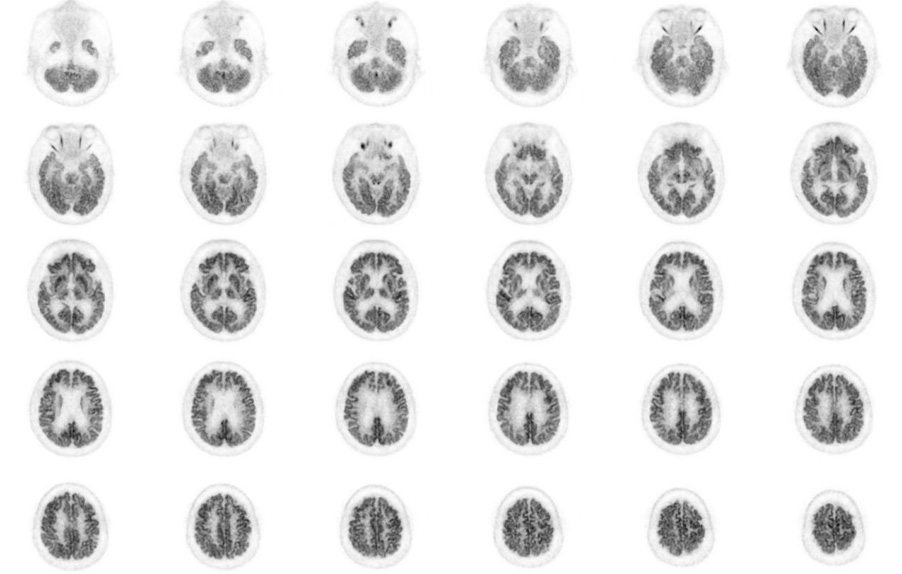

Head / Case2 : FDG

Axial

Courtesy : Kindai University Hospital

- Imaging protocol

- Injected dose: 3.29 MBq/kg, 18F-FDG

- Uptake time: 38 minutes

- Scan time: 30 minutes